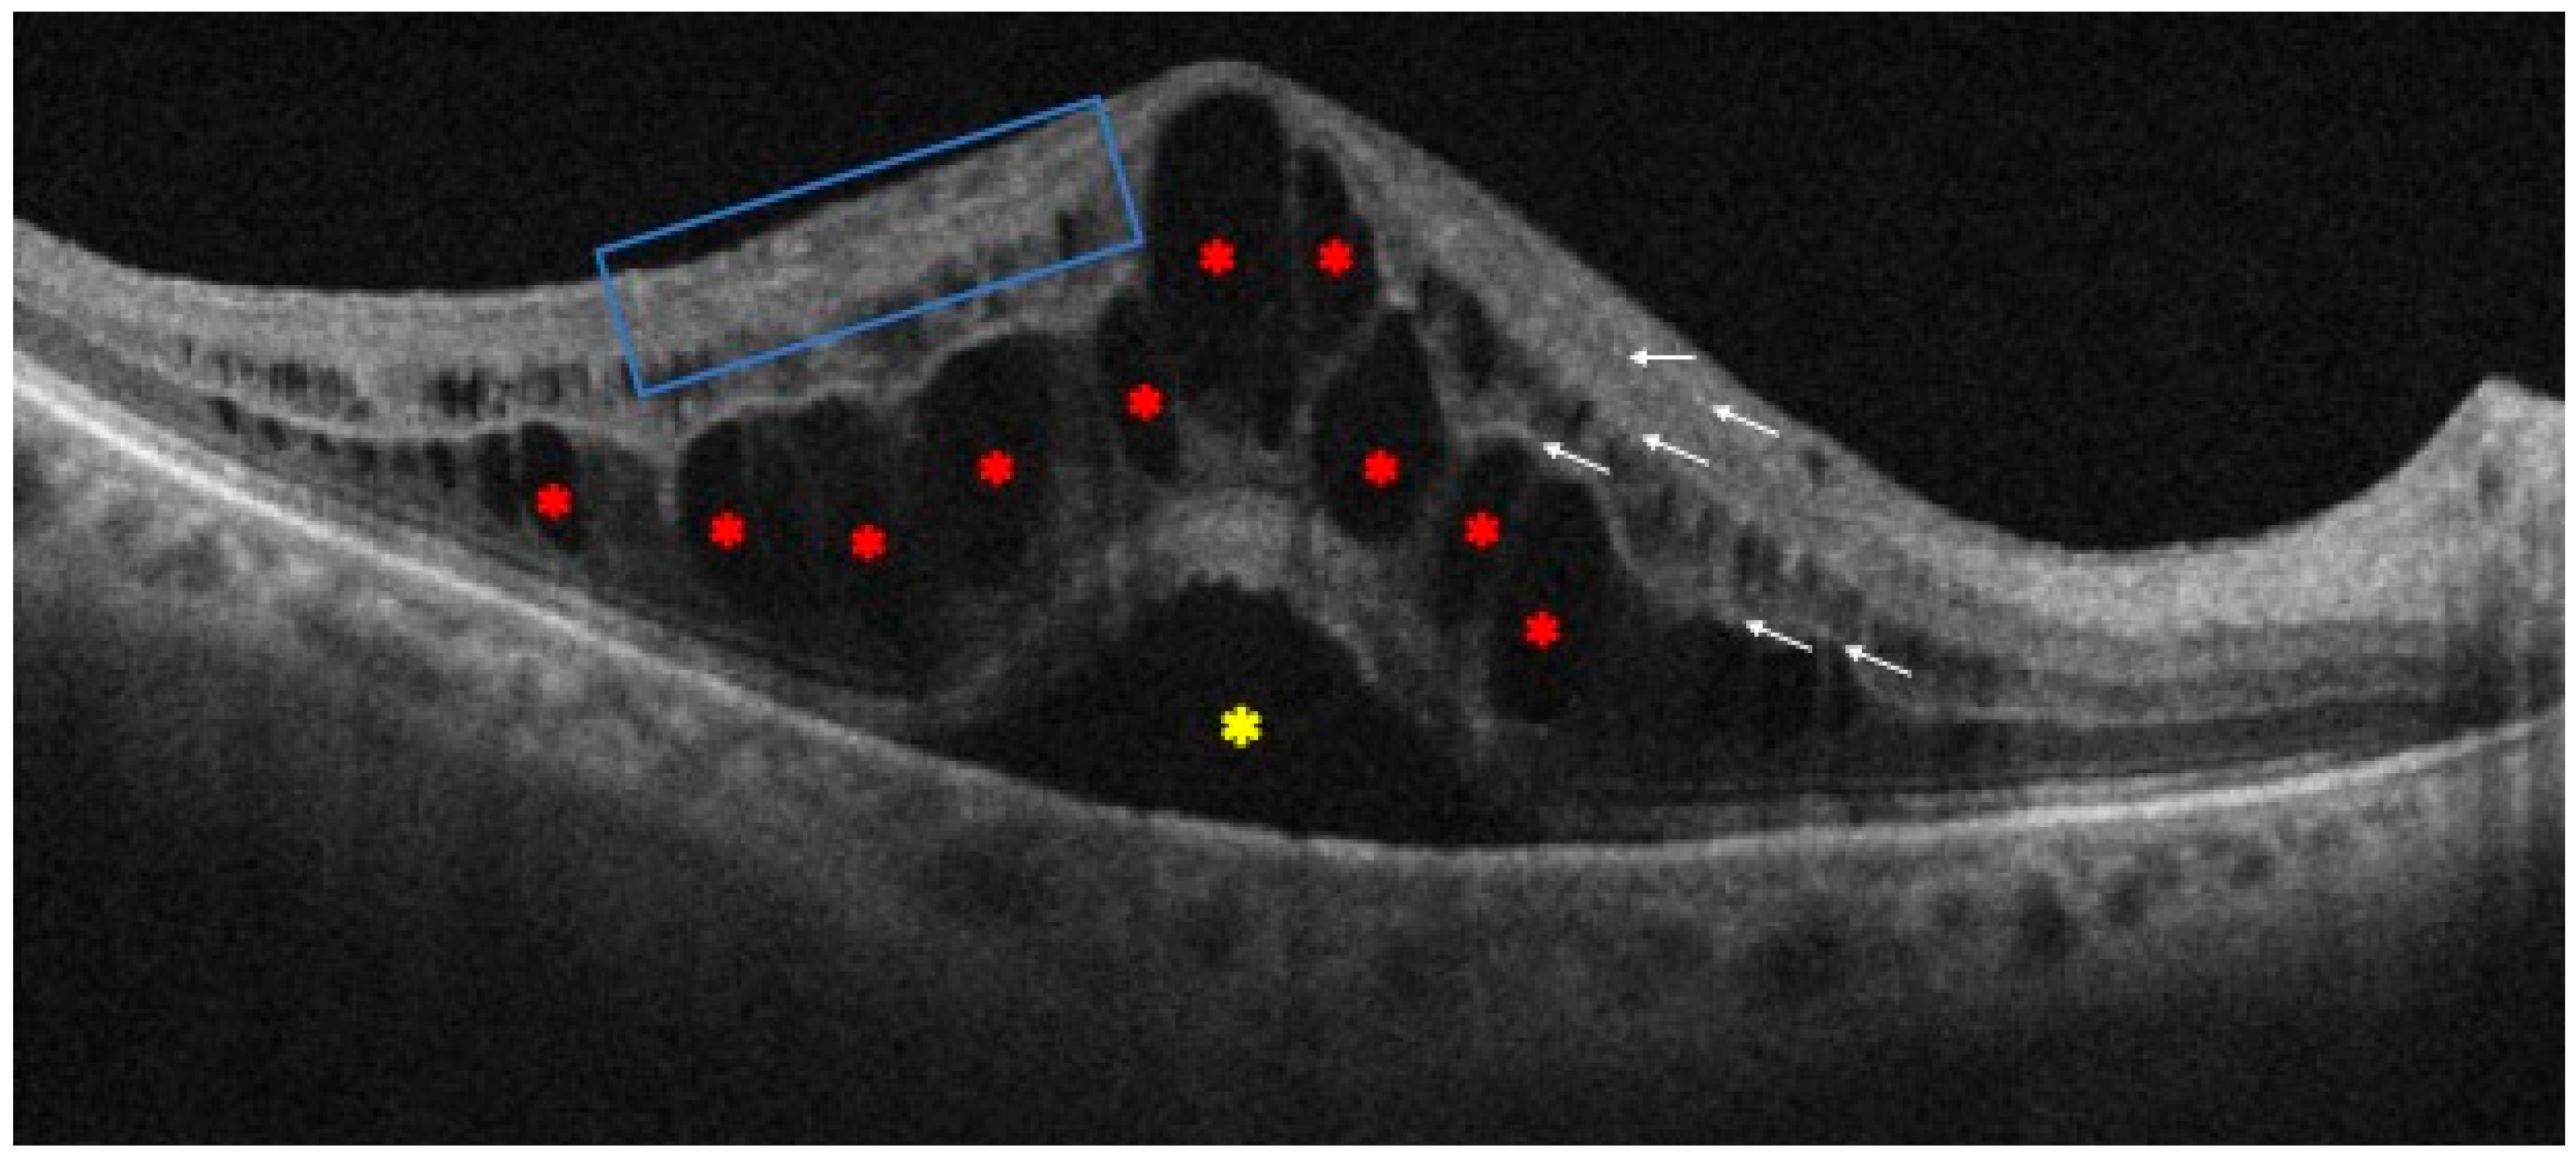

| Intraretinal cysts | Demonstrate the presence of macular edema, especially related to vasogenic effects |

| Central subfield thickness | Increased thickness correlates positively with worse visual outcomes |

| Disorganization of retinal inner layers | Its morphological extent is linked to the degree of vision loss, indicating the level of cell destruction |

| External limiting membrane rupture | Associated with worse visual outcomes |

| Ellipsoid zone disruption | Associated with worse visual outcomes |

| Hyperreflective foci | Inflammation biomarker associated with worse visual outcomes, most likely due to damage to the photoreceptor layer |

| Subretinal fluid | Inflammation biomarker frequently seen at presentation, but it does not consistently indicate long-term functional or anatomic outcomes |